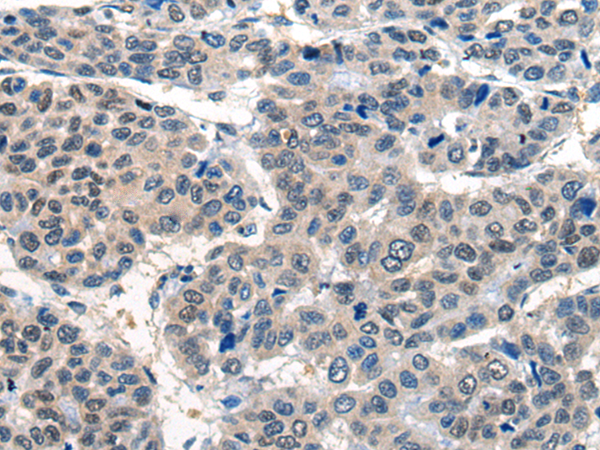

分类: 科研抗体货号: P11068别名: NR1, MRD8, GluN1, NMDA1, NMDAR1应用: IHC反应种属: Human, Mouse, Rat